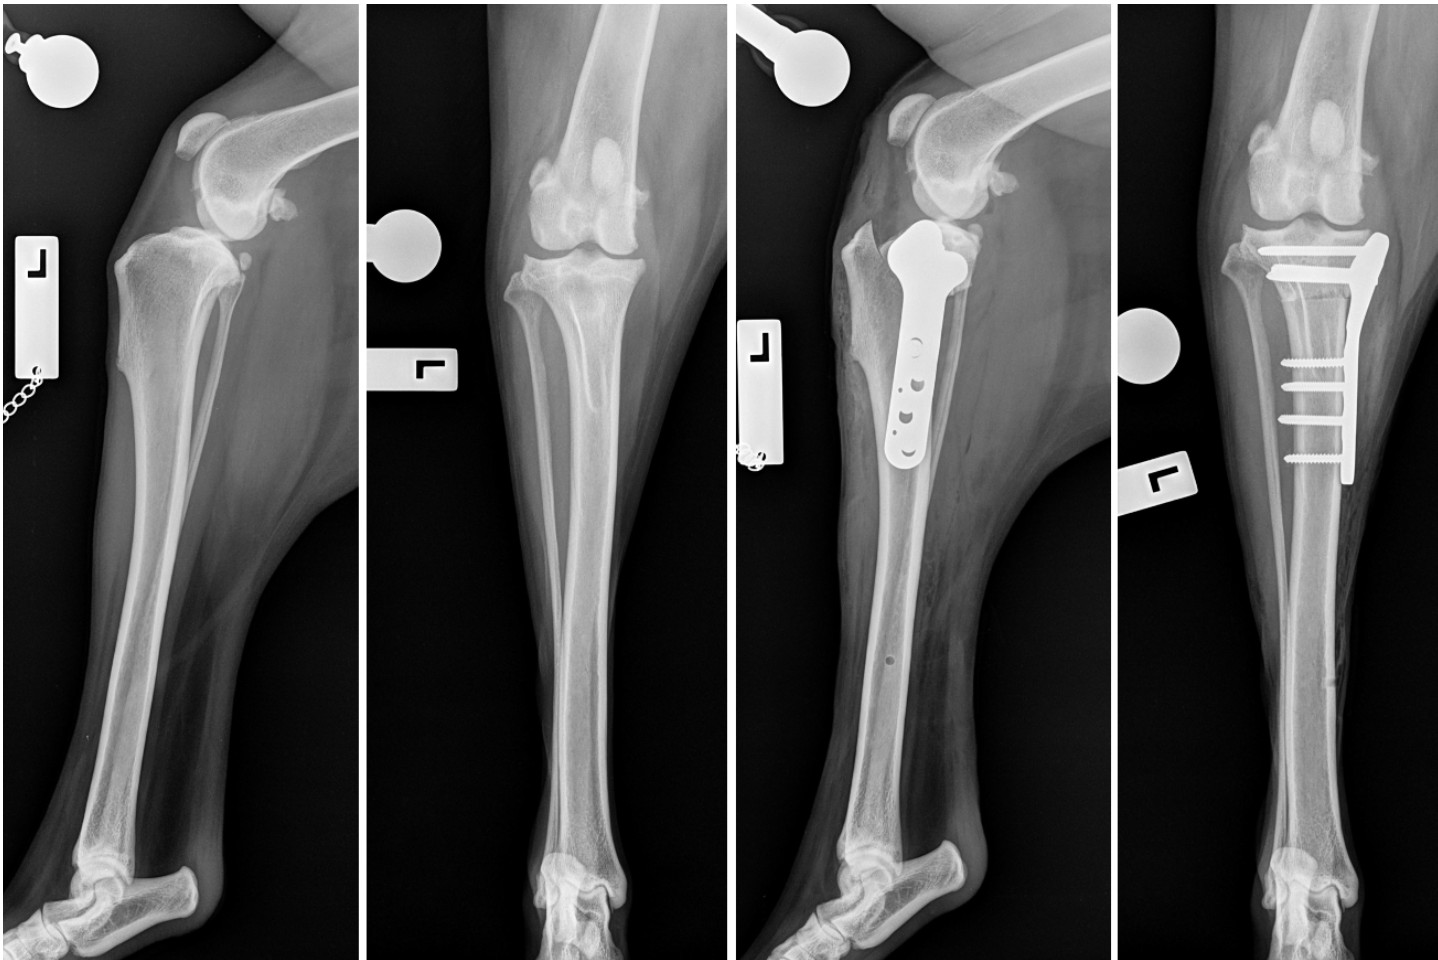

TPLO procedure – pre and postoperative radiographs